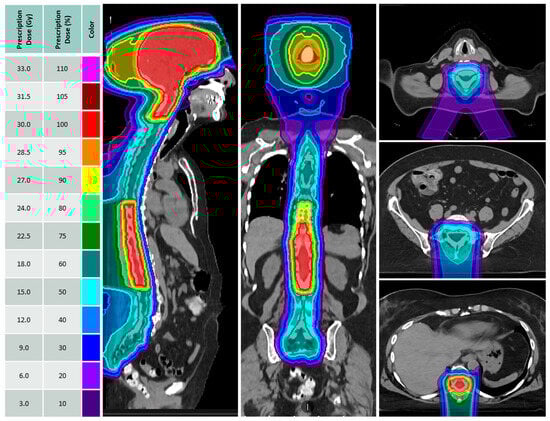

2.2. Treatment Planning and Delivery